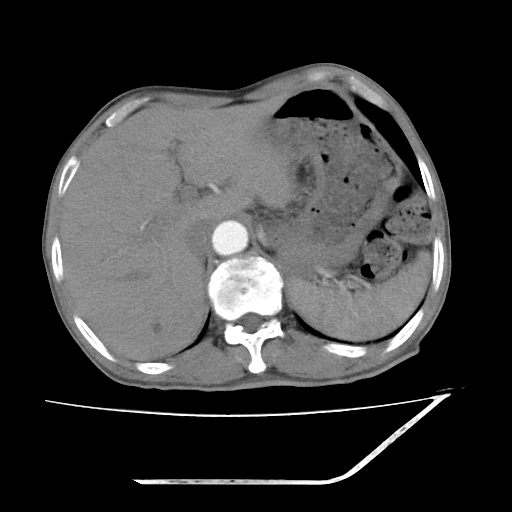

增强

考虑右肾盂癌,肾动脉受侵,右肾功能减退,右肾盂输尿管积水,管壁增厚,考虑种植转移,应该把下面扫完的

支持右侧肾盂癌伴肾静脉瘤栓形成可能性大,右肾结石.肝右叶后段低密度影,不除外转移.

考虑右肾盂癌,肾动脉受侵,右肾功能减退,右肾盂输尿管积水,管壁增厚,考虑种植转移  支持

考虑右肾盂癌,右肾功能减退,右肾盂输尿管积水,管壁增厚,考虑种植转移  支持

右肾盂旁ca并肾静脉瘤栓形成/肾功能降低。

右肾结石。

右肾盂癌,肾动脉受侵,右肾盂输尿管积水,管壁增厚,考虑种植转移

右肾盂移行细胞癌并右输尿管中段转移.肾积水.

支持 右侧肾盂癌伴肾静脉瘤栓形成可能性大,右肾结石;肝右叶后段低密度影,不除外转移。

1.右侧肾盂癌伴肾盂积水。

2.肾脏功能减退,原因有:(1)肾动脉受侵。(2)肾静脉受侵(3)肾积水,等。本例,肾动脉显影较好,但受压明显;肾静脉无明显显示,受压或静脉癌栓,下腔静脉腔内未见明显充盈缺损。

3.右侧上段输尿管扩张,原因:(1)积水所致;(2)种植。